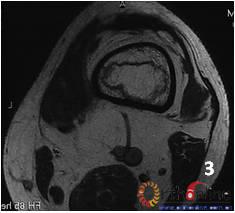

2.    发生在骨端(股骨头、肱骨头等)的坏死称为骨坏死(osteonecrosisON)。ON有两种类型:单纯骨髓坏死,软骨下骨(皮质骨)部分保留;骨髓坏死连同皮质坏死。

3 男,53岁,激素相关股骨头坏死,MRI2003年)示右侧L1型坏死(皮质存留,骨髓坏死),左侧L3型坏死(皮质及骨髓均坏死),三年后(2006年)及6年后(2009年),CT扫描示右侧股骨头维持圆形,骨皮质完整,但中央坏死灶未修复;左侧股骨头塌陷

Fig 3  Male, 53 year-old, steroid-associated ONFH, MRI(2003) showed type L1 necrosis(cortical bone was preserved, necrosis in bone marrow) in right side; type L3 necrosis(both cortical bone marrow) in left side. CT scan showed the right femoral head keep round, and collapse occurred in left femoral head three (2006) and six year (2009) later.

3.    两种类型的ON有不同的结局,前者预后较好,而后者预后差。(图3